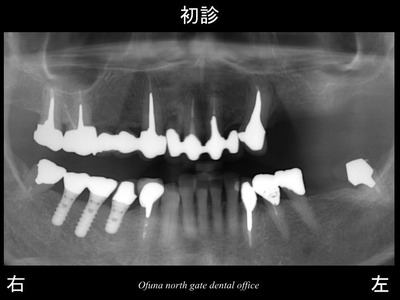

上顎の左側の奥歯が4歯分と

下顎の左側の奥歯が1歯欠損している患者様です。

以下が初診時のレントゲンになります。

歯が欠損しているわけですから

単に欠損部にインプラントを埋め込めば良いということになります。

なぜ前の歯科医院では 上顎左側の欠損部に

インプラント治療ができない と言われたのでしょうか?

ちなみに下顎右側の3本のインプラントは、他の歯科医院で行ったインプラントです。